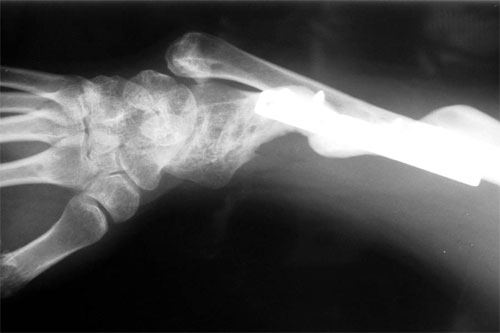

E.R. is a 26 year old male lifeguard who had a severe, unfortunate accident the first time he ever mounted a motorcycle. He was in a coma for many months with head trauma and had fractured his right elbow and forearm at the time of injury. He developed a condition called Heterotopic Ossification which meant that multiple joints «froze-up» due to deposits of calcium in the joint capsules. He was not able to walk until both hips were operated on by an internationally known hip surgeon who then referred him to Dr. Badia to address the stiff Right elbow and deformed forearm. In fact, at the initial visit, the patient stated that he had not moved the right elbow AT ALL for nearly 4 years and was unable to feed or groom himself with that hand. After a series of 3 operations to reconstruct both the elbow and forearm, this young man has gone back to swimming, work and a normal lifestyle.

The pictures depict the application of the dynamic external fixator, which stabilized and provided early motion to the rigid elbow after aggressive release of the capsule and bone excision.